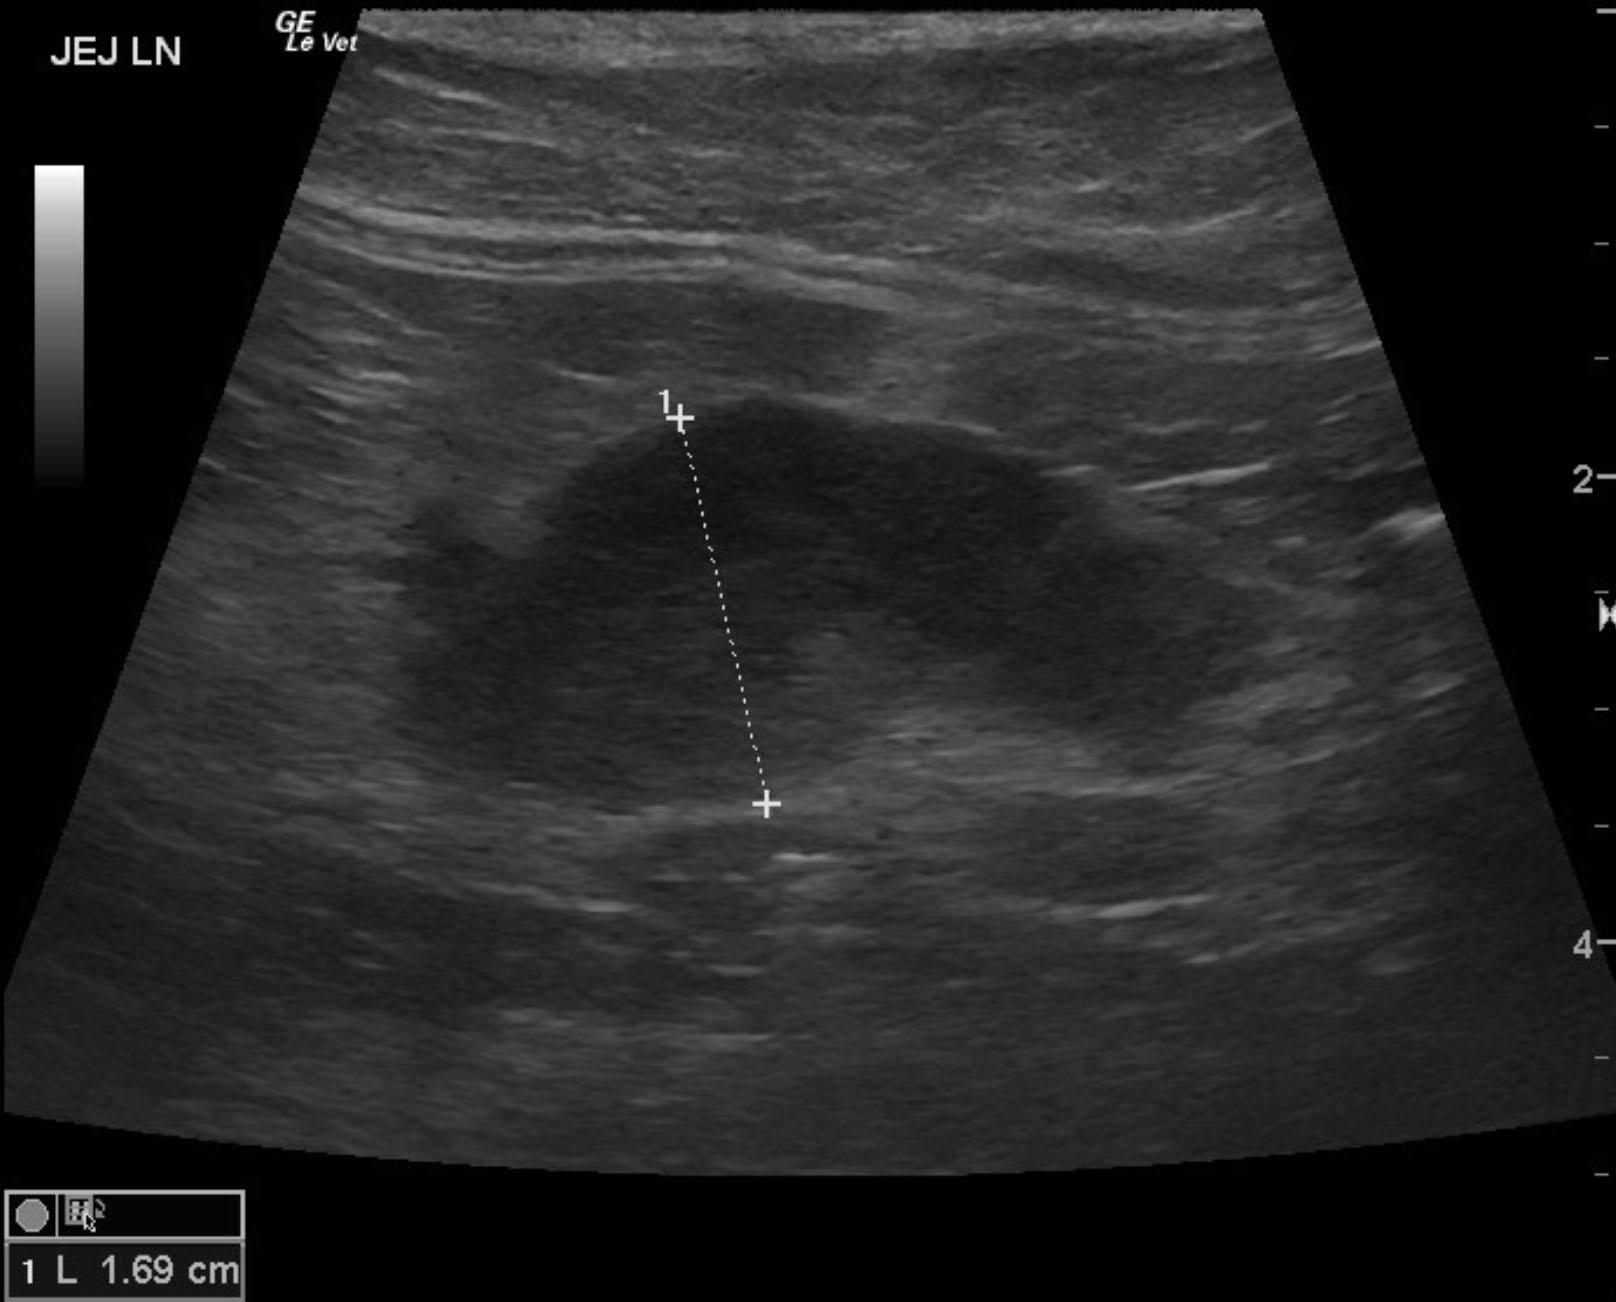

A 13-year-old SF DSH was presented for evaluation of 5-6 days of anorexia and weight loss. Abnormalities on physical examination were dehydration and dilated pupils. Urinalysis showed bilirubinuria. Abnormalities on serum biochemistry were elevated ALP activity and bilirubin.